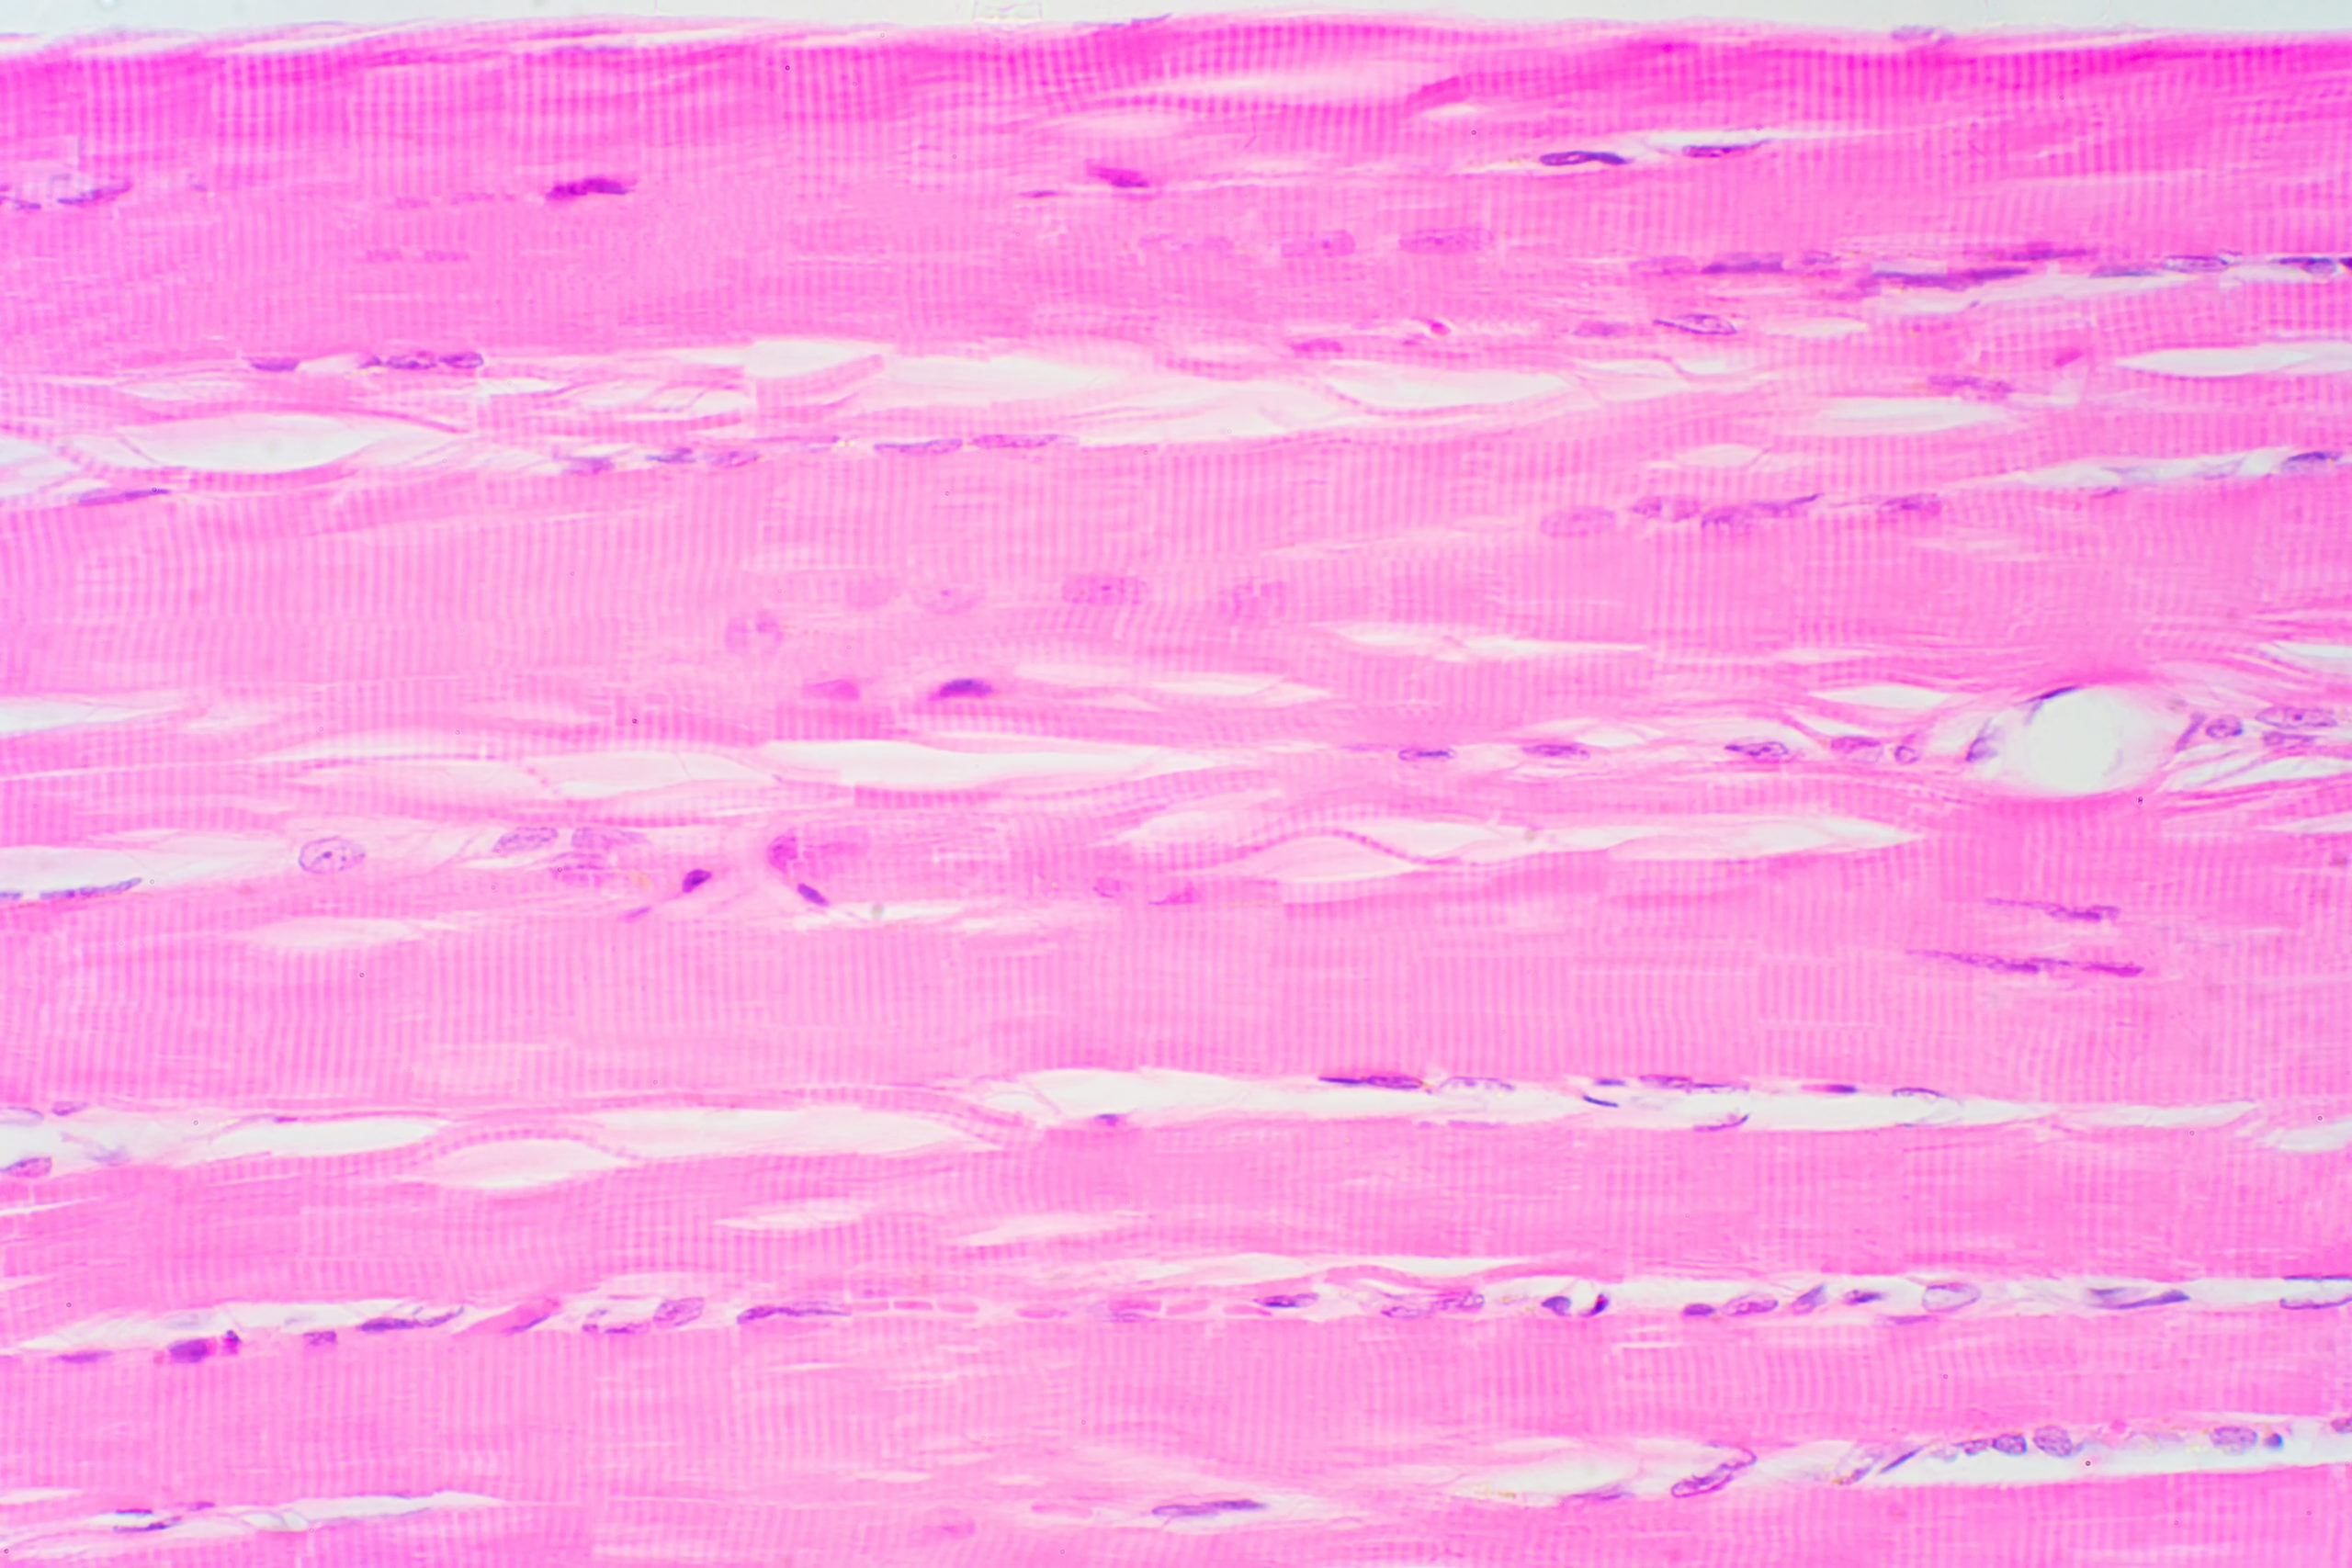

私たちの身体は自らの運動状態を正確に把握しながら動作を行う能力、すなわち“固有感覚”によって巧みにコントロールされています。その根幹を支えているのが筋肉の内部に埋め込まれた微細な感覚器官、筋紡錘です。筋紡錘は筋の長さやその変化速度をリアルタイムで感知し、中枢神経系へと情報を伝達する役割を担っています。これは動作の制御や姿勢保持、反射的な運動反応の精度を高めるうえで極めて重要な働きであり、身体の運動機能の精密な協調性に不可欠な仕組みです。

筋紡錘は主に2種類の求心性線維、すなわちIa線維とII線維によって構成されます。Ia線維は筋がどれだけ急激に伸びているかという“速度情報”を、II線維は“筋の長さそのもの”を中枢に報告します。これにより、筋紡錘は単なる受動的なセンサーではなく、筋の動的状態を時系列的に記録し、必要に応じた反射的反応の引き金として機能する高機能な制御機構となっているのです。

さらに興味深いのは、筋紡錘が自らの感受性を可変的に調整できる点にあります。その調節を司るのがγ運動ニューロンの存在です。筋紡錘内の筋線維(=核鎖線維および核袋線維)は、通常の随意筋とは異なる特性をもち、γ運動ニューロンによって制御されています。γ運動ニューロンが活性化すると筋紡錘内部の筋線維が収縮し、感覚部が間接的に伸展された状態となります。これはつまり筋の実際の長さが変化していなくても、筋紡錘が興奮しやすくなることを意味しており、筋の動きや張力の変化に対する反応性が向上するというわけです。